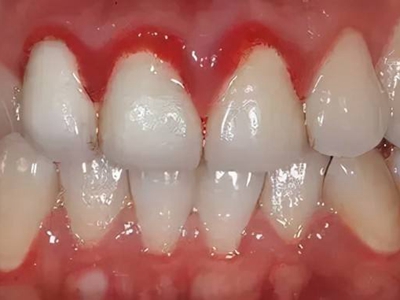

慢性龈炎又称边缘性龈炎或单纯性龈炎,主要表现为游离龈和龈乳头因炎性水肿,而变为鲜红或暗红色,龈缘变厚,龈乳头圆钝肥大。慢性龈炎的患病率高,治愈后仍可复发,部分患者可发展成为牙周炎。

慢性龈炎的病损部位一般局限于游离龈和龈乳头,以前牙区为主,尤其以下前牙区最为显著,患者常因刷牙或咬硬物时牙龈出血而就诊。游离龈和龈乳头颜色变为鲜红或暗红色,病变较重时炎性充血可波及附着龈。龈缘变厚,龈乳头圆钝肥大,可增生呈球状,覆盖牙面。牙龈松软脆弱,缺乏弹性。

当牙龈以增生性反应为主时,龈缘和龈乳头呈坚韧的实质性肥大,质地较硬而有弹性。龈沟液量增多,还可能出现龈沟溢脓现象。